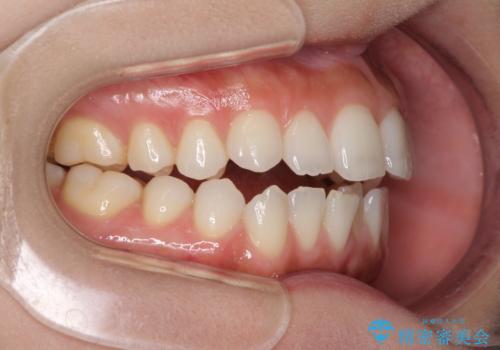

前歯のオープンバイトを治したい インビザラインでの矯正治療

- 前歯の上下スペースによる話しにくさと顎への負担を気にして来院された患者様です。

インビザラインにより上顎の大臼歯を圧下し、上下の前歯の隙間を閉じていくこととしました。

上顎の奥歯を圧下させることで、上下前歯を接触させるように計画しました。

前歯が急に接触するようになり、慣れるまで時間がかかりましたが、前歯でものが咬めるようにもなり、患者様には大変満足していただきました。